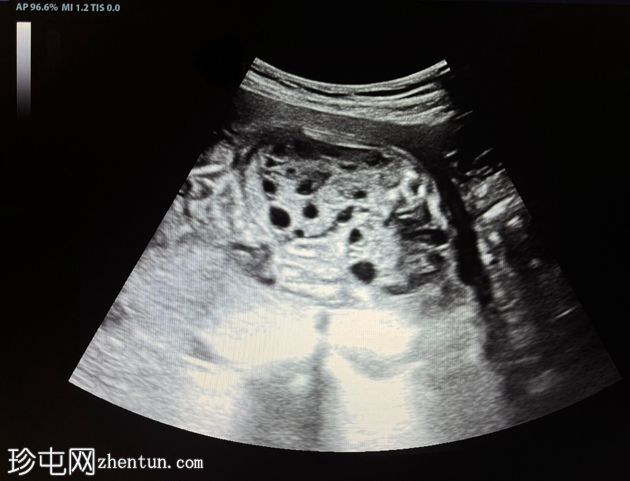

纵切面

胎儿双肾增大,回声增强,伴多发性小实质囊肿

羊水过少,羊水指数(AFI)= 3cm(未显示)

上述特征符合常染色体隐性多囊肾病的诊断。